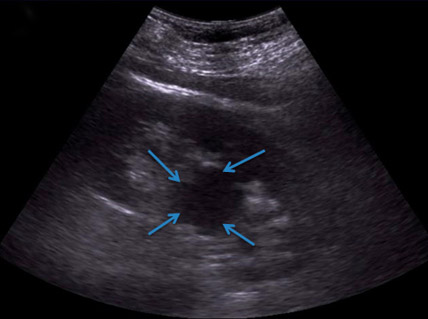

- УЗИ почек. Позволяет выявить округлое образование, расположенное в паренхиме органа или вне его.